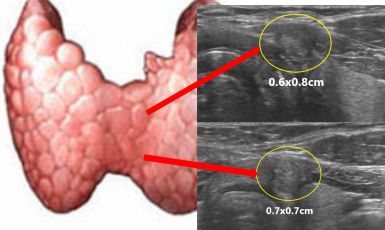

309번째 갑상선암 진단사례 (2019년8월30일) 목에 단단한 멍울이 만져지고 지속적으로 원인모를 불편한 증상이 지속되어 진료위해 내원한 환자분이셨습니다. 진찰상 앞쪽 ..

작성자 레이디유 작성일 09-24 조회 5